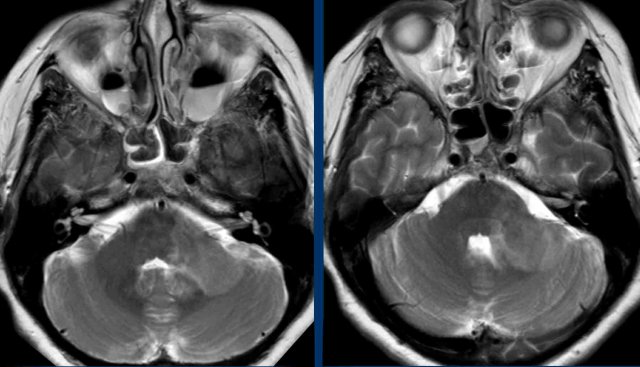

Images

This was a limited scan protocol (T2W and DWI) only to find out if there was any sign of ischemia.

There was no diffusion restriction (not shown) and acute ischemia was ruled out.

There is a large lesion with only limited mass-effect in the left cerebellar peduncle and there are bilateral air-fluid levels in the maxillary sinuses.

Continue with the follow up scan two days later...

First look at the four images.

What are the findings and what is your differential diagnosis?

You can click on the images for an enlarged view.

1. Lesions in both cerebellar peduncles, which means enormous progression in two days.

2. Peripheral enhancement of the lesion on the right (arrow).

3. Lesions in both thalami

4. Lesions in the external capsule more on the left (right lower image).

5. Diffusion was still normal (not shown).

Discussion

With this kind of fast progression of the disease a tumor can be excluded.

The differential focussed on demyelinization and rhombencephalitis.

Rhombencephalitis is an inflammatory disease affecting the brainstem and cerebellum with a wide variety of etiologies, including infection, autoimmune diseases and paraneoplastic syndromes.

Continue...

Conclusion

Finally the most likely diagnosis was an inflammatory rhombencephalitis.

there was a slow recovery.